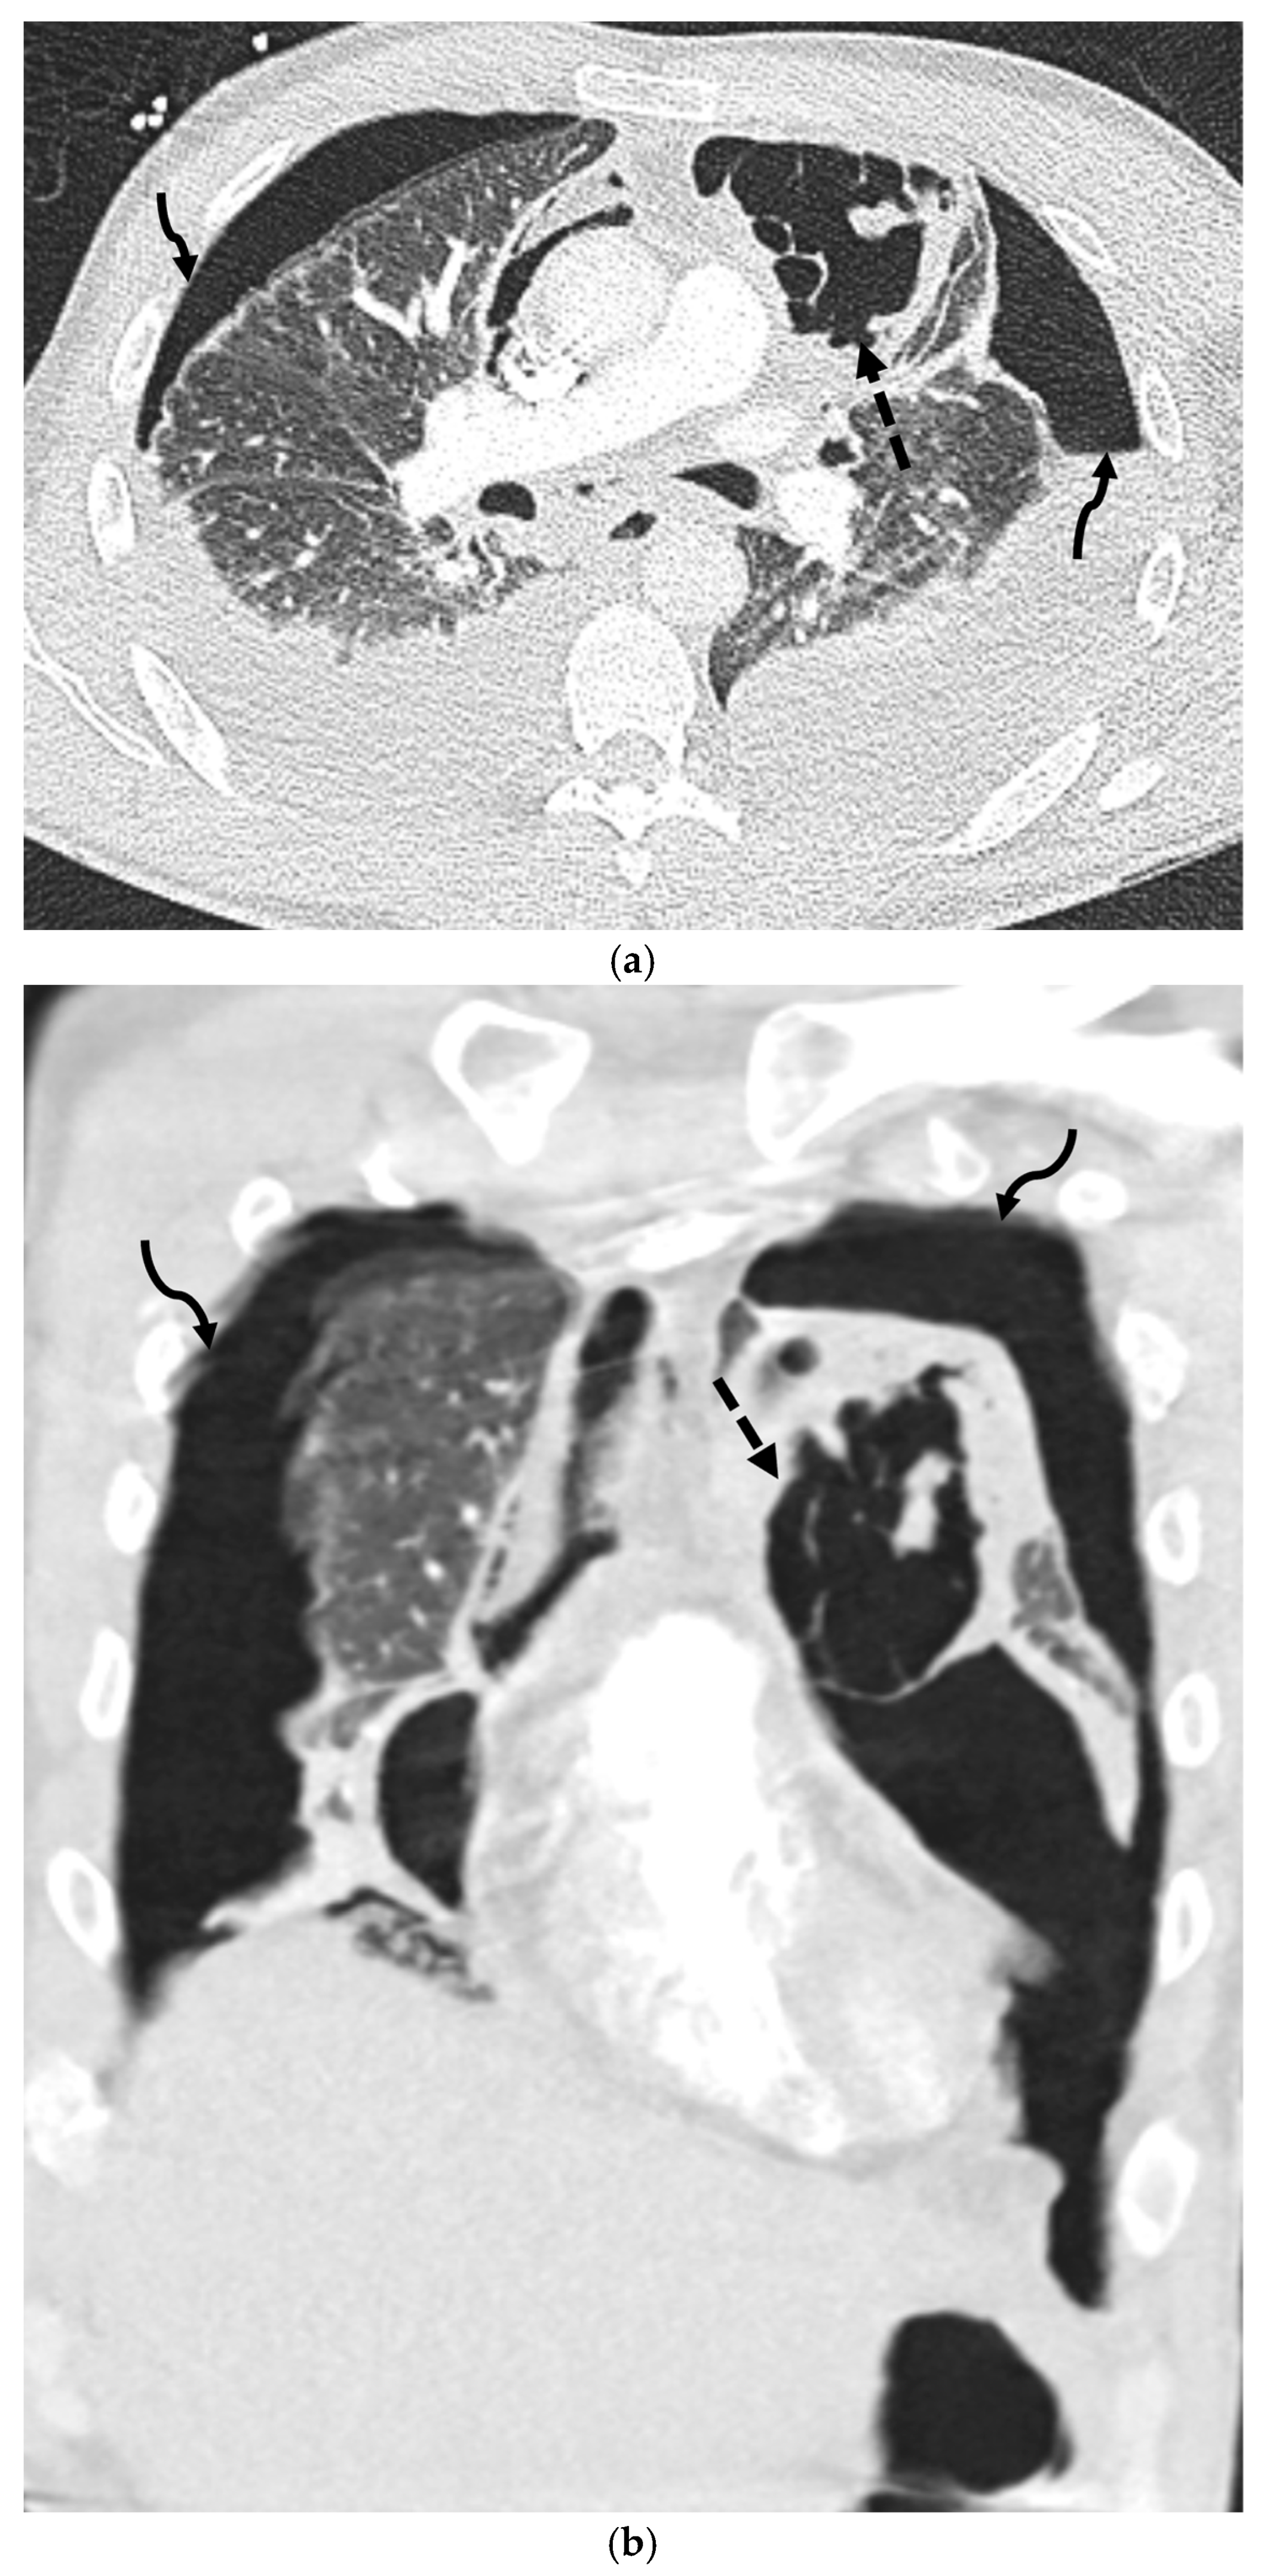

5.1.2. COVID-19 Pneumonia

5.1.3. Pneumocystis jirovecii Pneumonia (PJP)